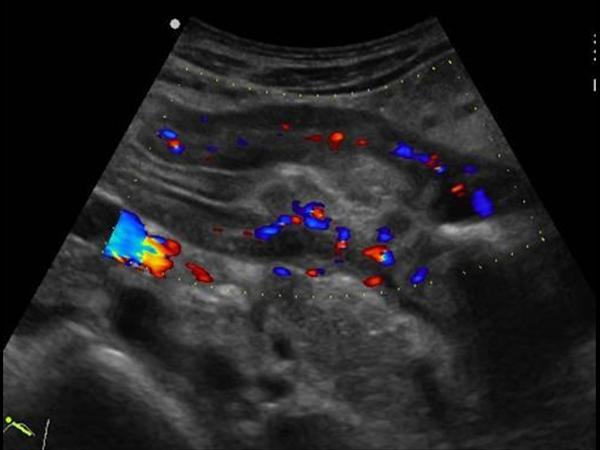

U dạ dày

» Thông tin: Nam giới – 41 tuổi.

» Lâm sàng: Đau thượng vị / Sút cân.